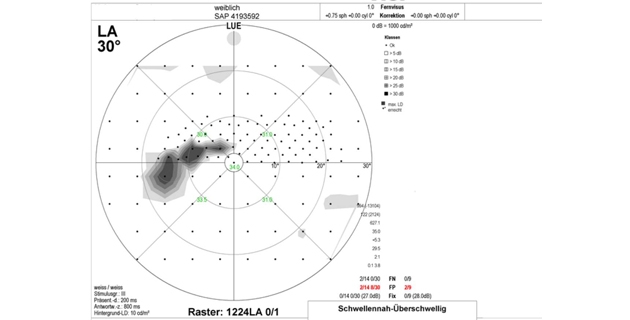

Da die Dicke der Hornhaut Einfluss auf die Augeninnendruckwerte hat, erfolgt zunehmend die Hornhautdickenmessung (Pachymetrie) zur kritischen Überprüfung der Werte. Hohen differenzialdiagnostischen Stellenwert haben auch die Beurteilung des Kammerwinkels (Gonioskopie) und des Sehnervenkopfes. Mittels optischer Cohärenztomographie (OCT) ist eine Quantifizierung des Verlustes an neuroretinalem Gewebe möglich. Die fotografische Dokumentation von Papille und Nervenfaserschicht erleichtert die Verlaufsbeurteilung. Die Gesichtsfelduntersuchung (Perimetrie) ist ein entscheidender Teil der Diagnostik.